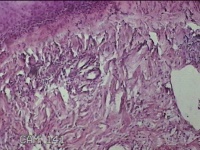

左侧腰部皮肤息肉组织

性别

男

年龄

40岁

临床诊断

皮肤和皮下组织良性脂肪瘤样肿瘤,其他部位的

一般病史

发现左侧腰部皮肤息肉组织5年余。

标本名称

大体所见

灰白暗红色息肉样组织1.7x1.3x0.3cm一块,表面糜烂,切面灰白暗红色,质软。